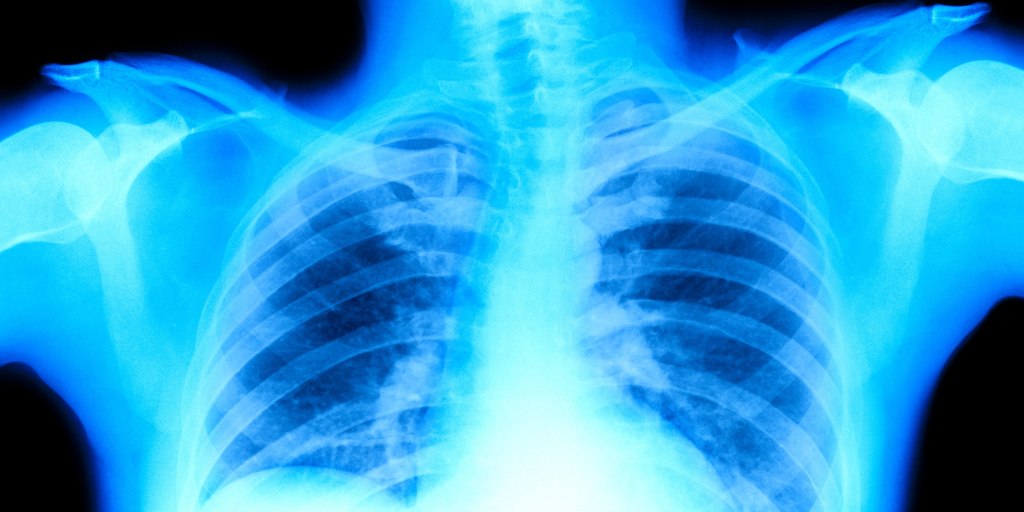

Dr. Humberto Choi emphasizes the importance of recognizing early symptoms of Lung cancer, which often goes undetected until its too advanced, making awareness critical.

- Dr. Humberto Choi, a pulmonologist at the Cleveland Clinic, highlights that Lung cancer is often diagnosed late due to its subtle symptoms that can mimic other conditions.

- Despite being the leading cause of cancer deaths in the U.S., many individuals fail to recognize early signs of cancer, leading to delayed treatment and poor outcomes.